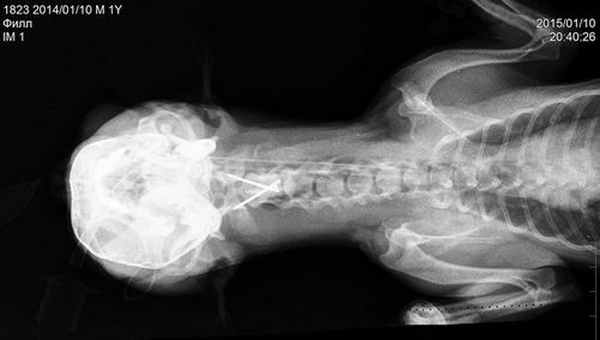

Краниография собаки с вентральной стабилизацией С1-С2.